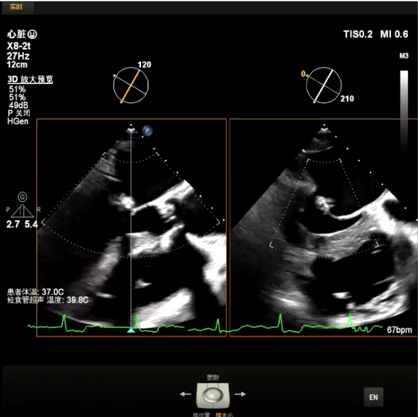

主动脉瓣狭窄(重度,跨瓣平均压差56mmHg),伴反流,主动脉瓣钙化,开放受限,有效开口面积0.6cm²;峰值流速4.56m/s,EF53%。经胸超声可见瓣膜开口严重受限,存在反流。